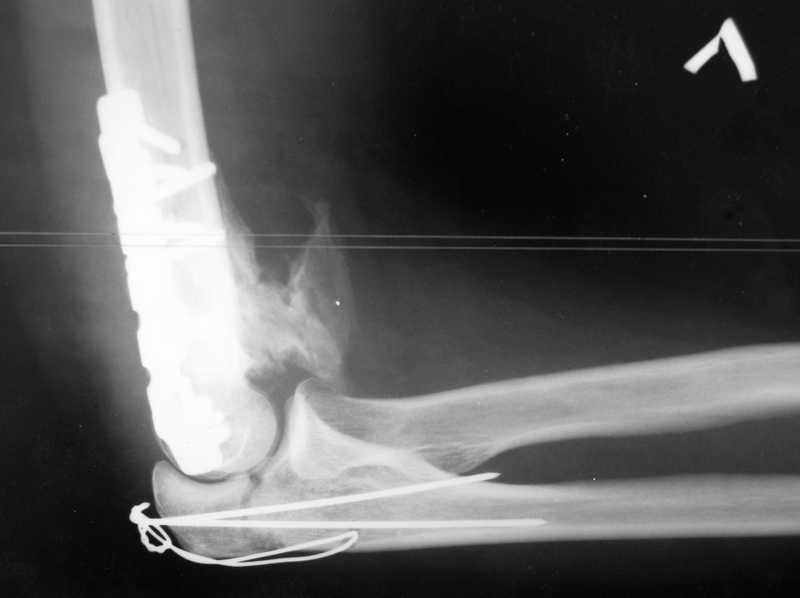

У пациентки 42 лет после операции остеосинтеза чрезмыщелкового перелома плеча, выполненной в нашей клинике 2 месяца назад, на контрольных R-граммах имеется гетеротопический оссификат по передней поверхности плеча. Оперирована по методике АО, после операции максимально рано начала заниматся ЛФК. В настоящее время основная жалоба пациентки на ограничение сгибания в локтевом суставе. Клинически объем движений: сгибание 90 градусов, разгибание 170 градусов, ротационные движения в полном объеме. Привожу снимки сразу после операции и через 2 месяца. (На рентгенограммах после операции в мягких тканях по передней поверхности плеча имеется небольшой костный фрагмент, но его ширина во фронтальной плоскости не более 1 мм., обнаружен был по снимкам после операции. Интраоперационно основные крупные фрагменты отрепонировались хорошо, объем движений был сгибание до 75 градусов, разгибание 175 град.) Пациентка неудовлетворена объемом сгибания, хотя была предупреждена о высокой вероятности ограничения движений. Профилактика гетеротопической оссификации (прием индометацина) не проводилась, т.к. имелась язвенная болезнь, да и эффект от его приема считаю сомнительным. Вопросы: 1.Стоит ли вмешиваться и пытаться удалить экзостоз? Если да,то в какие сроки и каким доступом лучше идти? 2. Оставить все как есть? 3. Не поможет ли ударно-волновая терапия либо какая-то другая методика? Буду благодарен за все ответы и оценки своей работы. С таким осложнением столкнулся впервые.

В данном случае лучше ни чего не трогать до года, произойдет консолидация, затем при удалении металла можно будет сделать артропластику с удаление оссификата и освободить передний отдел, а возможно к тому времени и задний. Пациентка должна поддерживать имеющийся объем движений.

Доступ обычно наружно-боковой без опаски, если не удается все достать, то внутренний боковой с выделением локтевого нерва(безопасней и спокойней). ФЗТ на локтевом суставе обычно без эффекта.